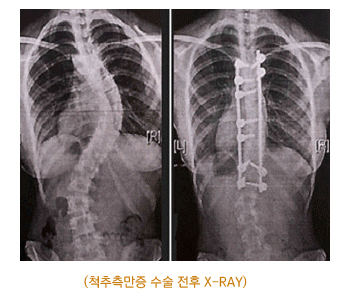

*진 단척추측만증은 대부분 일반 X-RAY 촬영으로 종류와 측만의 정도를 알 수 있습니다. 보통 일자로 되어 있어야 할 허리뼈가 척추측만증 환자의 경우 C자형이나 S자형으로 변형된 것을 확인할 수 있습니다. 휘어진 각도가 10도 이상이면 척추측만증이 진행중인 것으로 진단할 수 있습니다.

*치 료특발성 척추측만의 경우에는 3~4개월 주기로 관찰을 하고 20~40도는 보조기를 이용한 치료를 할 수 있습니다. 그러나 측만의 각도가 40도 이상인 경우에는 수술적 치료가 필요합니다. 하지만 성장기 청소년의 경우 척추측만증을 조기에 발견하여 수술적인 방법보다는 교정 치료를 통해 치료해 나가는 것이 중요합니다.